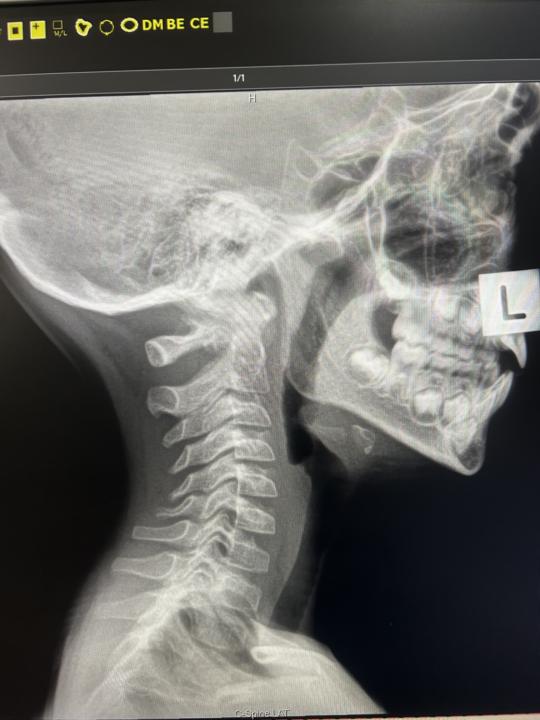

6yo with headaches and neck pain

6 yo with neck pain and spasm- getting frequent headaches and migraines Referred him to see a dentist due to the X-rays- any other recommendations